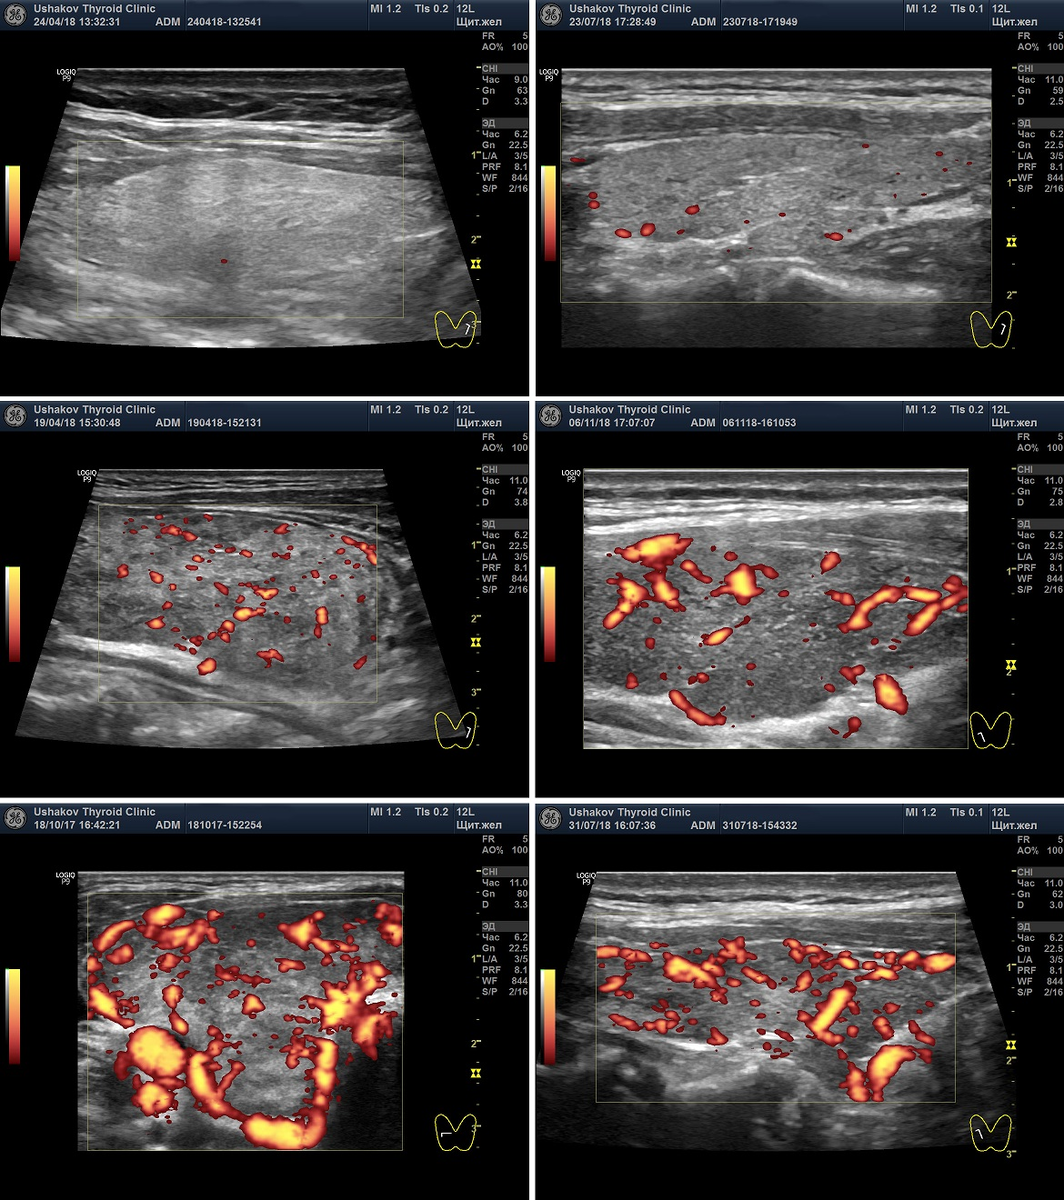

Очень важно в режиме ЦДК или ЭДК при УЗИ определить величину интенсивности кровотока. Не просто - "без изменения" или увеличен, а насколько увеличен.

Интенсивность кровотока (врачи пишут - васкуляризация) прямо указывает ан величину напряжения щитовидной железы!!! Это исследование не проводят около 50-60% узистов и ошибочно выполняют 40-49% других врачей УЗД. Не сопровождают Протоколы УЗИ снимками о кровотоке где-то 95% специалистов УЗИ.